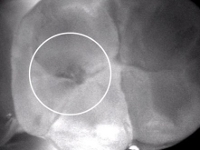

The detection of carious lesions and cracks at an early stage is necessary in order to implement prophylactic, or minimally-invasive and pain-free treatment. In daily practice, the diagnosis of initial lesions is not always simple.

The new KaVo DIAGNOcam is the first camera system that uses the tooth's structure to verify caries diagnosis. To do this, the tooth is transilluminated utilising light of a specific wavelength (780 nm generated by a led laser) and used like a light conductor. A digital video camera records the image and displays it live on a computer screen. Carious lesions are displayed as dark shadows. With its DIFOTI technology (Digital Imaging Fiberoptic Transillumination), DIAGNOcam offers high diagnostic safety which is comparable or superior to X-ray diagnosis in many cases, in particular with regard to approximal and occlusal caries. Furthermore, it is possible to show certain kinds of secondary caries and cracks. The X-ray free device thereby allows early and very gentle caries detection.